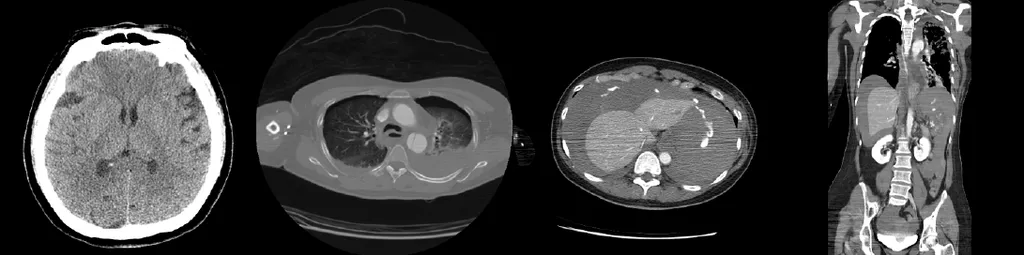

【111-1 醫學(五) 第4題】一位53歲女性駕駛小轎車與對側高速來車相撞,立刻被緊急送至第一級(Level I)創傷中心急救。到院時意識狀態清楚,主訴兩側胸部及腹部疼痛、兩側手腕及左下肢劇痛。理學檢查發現血壓80/50 mmHg、心跳115次/分、呼吸20次/分,給與氧氣5公升/分鐘使用後,動脈血氧飽和度可達98%;另左胸呼吸音減低,腹部微脹有明顯瀰漫性壓痛,雙側手腕變形及左股骨開放性骨折。經快速大量輸液治療後血壓上升至100/55 mmHg,故安排緊急全身顯影電腦斷層,結果如附圖。病人送回急救區後發現意識模糊,但對深痛刺激有反應,生命徵象為血壓60/40 mmHg、心跳125次/分、呼吸20次/分,動脈血氧飽和度無法偵測。下列何種醫療處置較為適當?

這題的解題核心在於判斷病人休克惡化的最主要原因,並根據影像學證據採取最緊急且能挽救生命的處置。圖片中腹部電腦斷層顯示脾臟嚴重撕裂傷伴隨大量腹腔內出血,這是導致病人休克惡化的關鍵原因,需要立即手術止血。